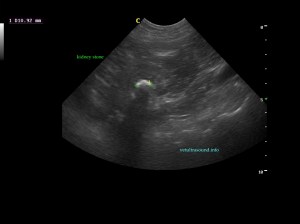

Ευρήματα: Παρουσία λίθου στην πύελο του αριστερού νεφρού ο οποίος καταλάμβανε όλη την κοιλότητά της και εκτεινόταν στο πρώτο τμήμα του ουρητήρα. Ο λίθος προκαλούσε ήπια διάταση του πυελοκαλυκικού συστήματος και του ουρητήρα. Αντίστοιχα στον δεξιό νεφρό βρέθηκε λίθος ο οποίος εντοπιζόταν μόνο στην κοιλότητα της νεφρικής πυέλου. Στην ουροδόχο κύστη βρέθηκε μικρή παρουσία ιζήματος.